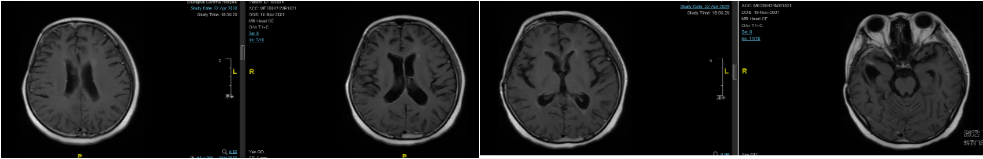

图2. 2017年4月6日放疗期间复查头颅MRI,提示强化灶有缩小